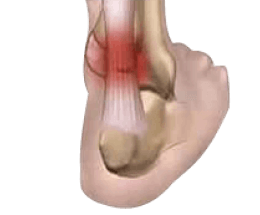

Bursitis

Bursitis is the inflammation of the bursa, a sac filled with lubricating fluid, which decreases rubbing, friction, and irritation, acting as a cushion between bones and other moving body parts such as muscles, tendons, or skin. In the ankle, the retrocalcaneal bursa, located at the junction of the Achilles tendon with the heel bone, is the most common site of bursitis. Inflammation of this bursa can be caused by overuse and is often linked to Achilles tendinitis.

Ankle bursitis causes pain and tenderness around the ankle. It can be treated through rest, ice, compression of the area, and elevation of the ankle (RICE). Pharmacological approaches include NSAIDs, such as ibuprofen and naproxen, or local corticosteroid injection with ultrasound guidance to the affected area can be very helpful in reducing pain and inflammation due to bursitis.